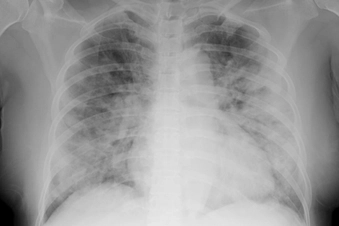

Shortness of Breath

Colds can cause a very stuffy nose, which make breathing a little harder, but real shortness of breath is a sign of something more serious. It's a common symptom of asthma or a flare-up of COPD, and it also can be from a serious infection, like bronchitis, pneumonia, or COVID-19.